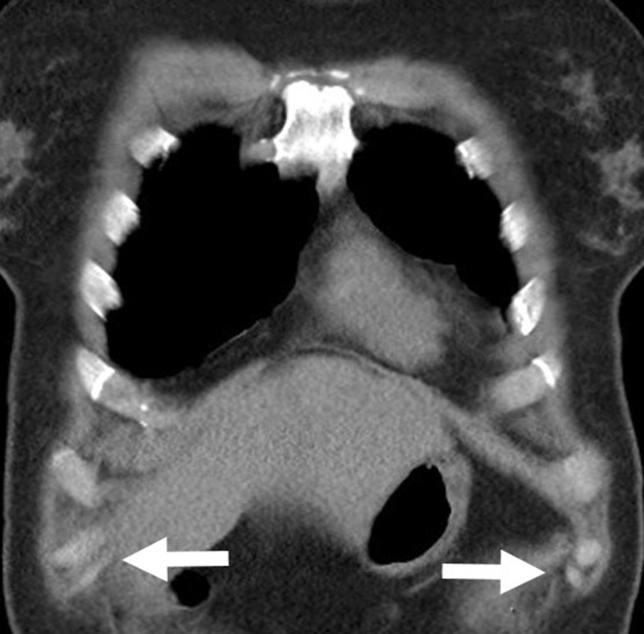

肋缘重建治疗滑脱肋综合征:500多例患者的治疗结果及对早期缝合修复技术的改进

Costal margin reconstruction for slipping rib syndrome: Outcomes of more than 500 cases and advancements beyond earlier sutured repair technique.

To evaluate results of sutured repair for slipping rib syndrome (SRS), identify failure points, and discuss technique modifications to improve outcomes through costal margin reconstruction (CMR).

Patients undergoing repair of SRS between February 2019 and February 2024 at an academic referral institution were retrospectively analyzed. Pain scores, quality of life, pain medication use, and reoperations were evaluated pre- and postoperatively at 1 and 6 months. In patients failing sutured repair we identified specific failure points and devised a new CMR technique to overcome them. Subsequent CMR patients were followed at 1, 6, 12, 18, and 24 months using the same outcome measures.

Four hundred forty-nine patients underwent repair. Two hundred forty-one patients underwent sutured repair with revision required in 66. Median time to revision was 14 months. CMR was developed and performed in 247 patients. In CMR patients, preoperative mean pain score of 7.5 out of 10 dropped postoperatively to 4.0, 2.5, 1.9, 1.3, and 0.9 at 1, 6, 12, 18, and 24 months, respectively ( < .001). Mean quality of life of 38% improved to 73%, 83%, 88%, 93%, and 95% at the same intervals ( < .001). Preoperatively, 29% of patients chronically used opioid medications. Opioid use dropped postoperatively to 11%, 4%, 4%, 0%, and 0% at the same intervals. Use of nonopioid medications followed a similar pattern. One CMR patient required full revision.

SRS is a debilitating, but correctable disorder. Improved pain and quality of life, reduction in chronic opioid use, and freedom from revision surgery suggest that CMR should be considered the standard operation for SRS.